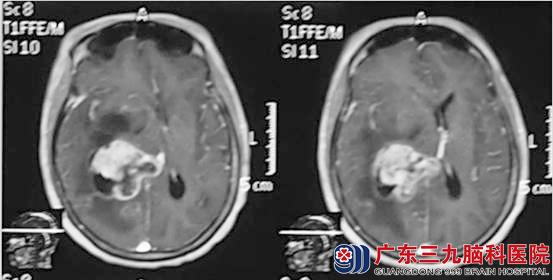

9月初,林女士突感头痛,症状逐渐加重,并伴有恶心呕吐,头颅CT提示:右侧基底节区占位并囊肿,考虑转移瘤。?xml:namespace>

术后第三天,林女士急诊行挽救性X刀治疗。之后状态明显好转,神志清楚,对答切题,能自主行走,头晕头痛的症状消失。在X刀治疗后5天,林女士复查头颅CT,显示右侧囊肿基本消失并拔除引流管。

治疗前

治疗后